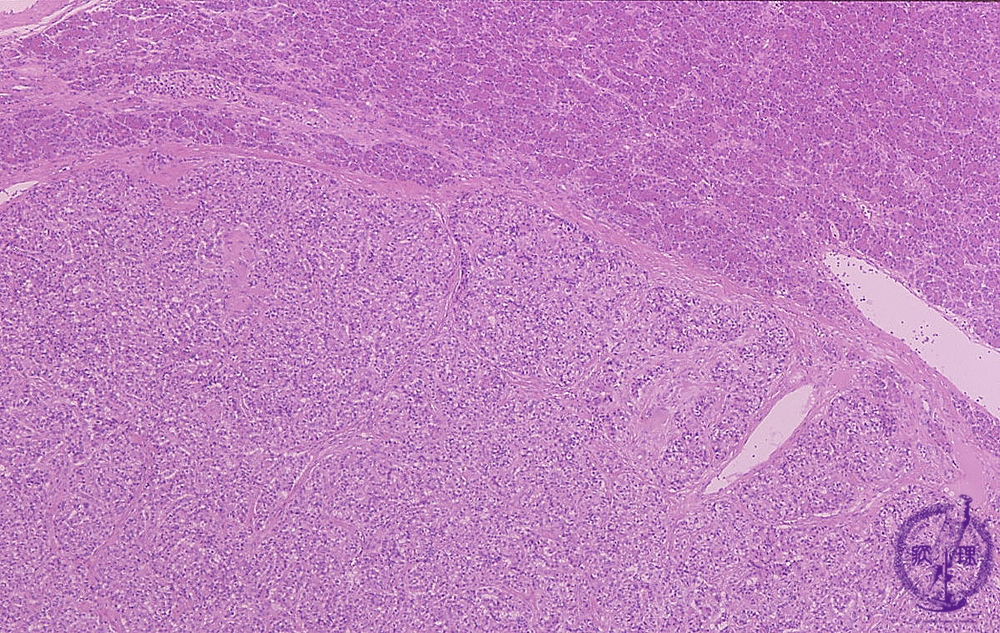

Microscopic findings (HE stain, low power view). Thin fibrous capsule present around the tumor (dotted line).